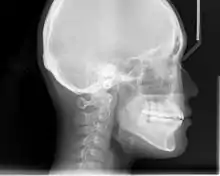

In the postwar period, cephalometric radiography[12] started to be used by orthodontists for measuring changes in tooth and jaw position caused by growth and treatment.[13] The x-rays showed that many Class II and III malocclusions were due to improper jaw relations as opposed to misaligned teeth. It became evident that orthodontic therapy could adjust mandibular development, leading to the formation of functional jaw orthopedics in Europe and extraoral force measures in the US. These days, both functional appliances and extraoral devices are applied around the globe with the aim of amending growth patterns and forms. Consequently, pursuing true, or at least improved, jaw relationships had become the main objective of treatment by the mid-20th century.[6]